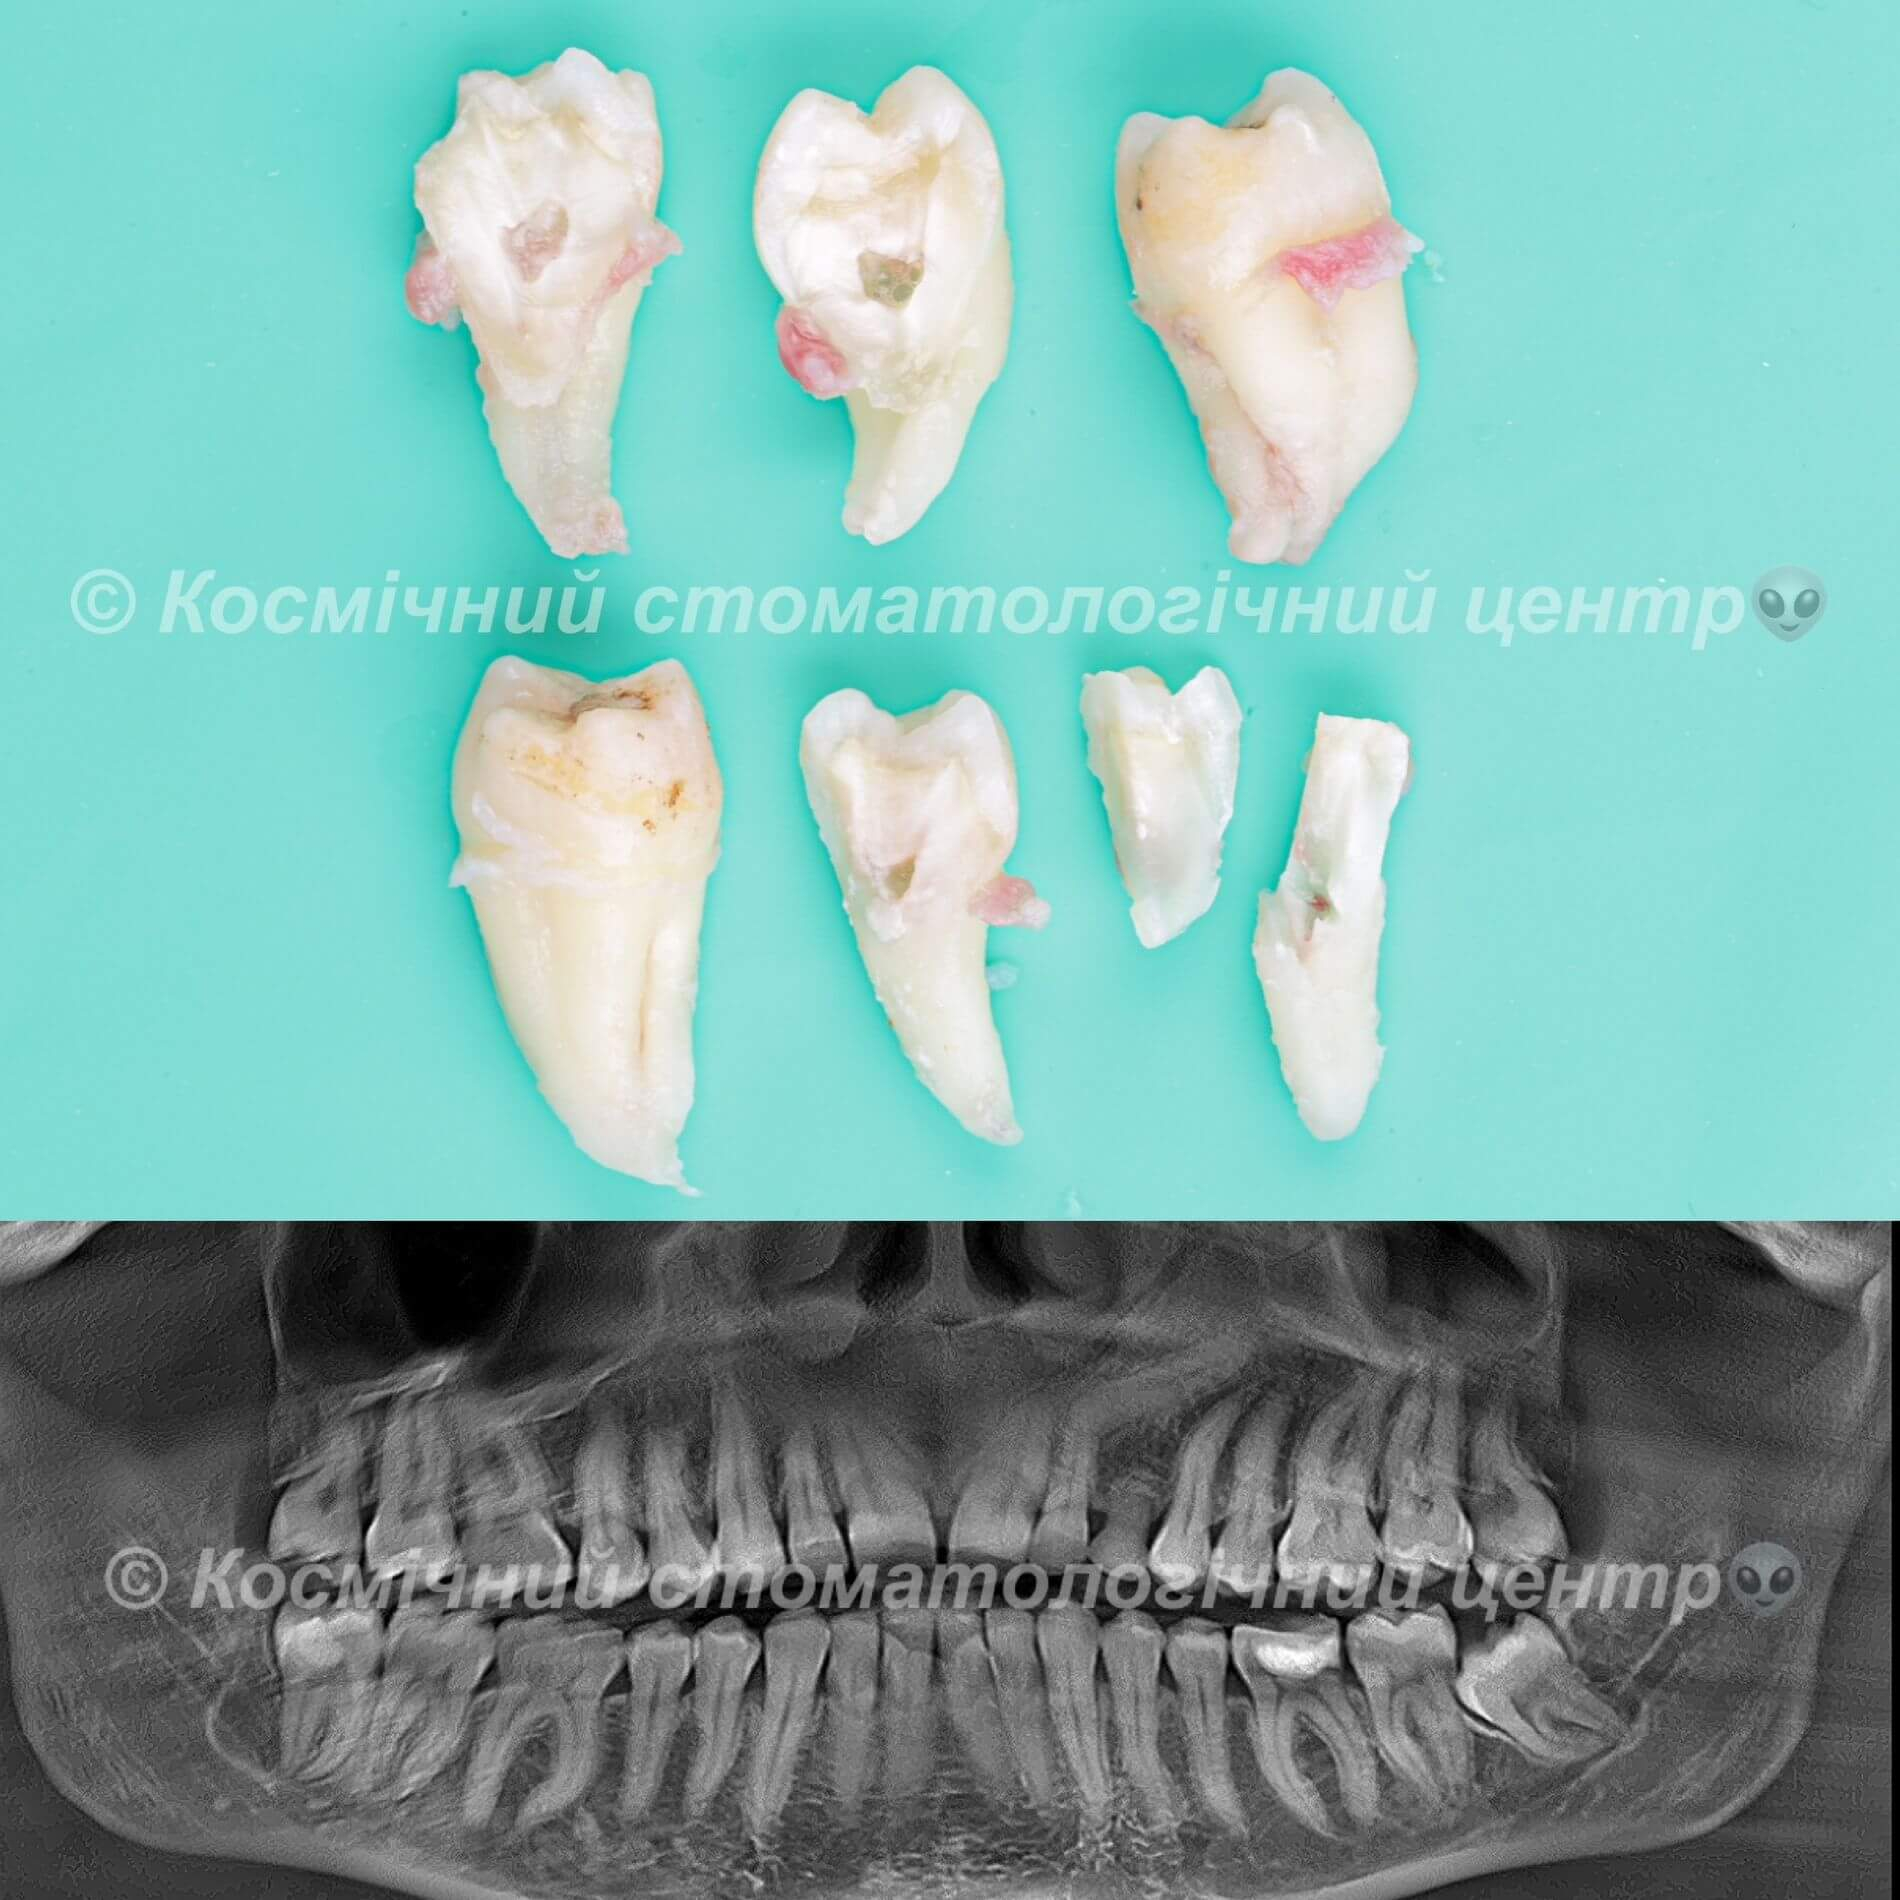

Галерея